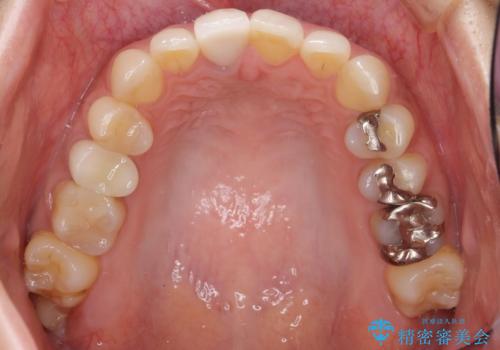

前歯のクラウンは一度修正し、患者様の理想とする色味や形態を追求しました。

天然歯と見紛うほどの自然な仕上がりに喜んで頂けました。

ジルコニアクラウンの繊細なグラデーション・透明感は熟練した技工士さんの技術の賜物です。

右上1:ジルコニアクラウン スペシャル

右上5:ジルコニアクラウン スタンダード